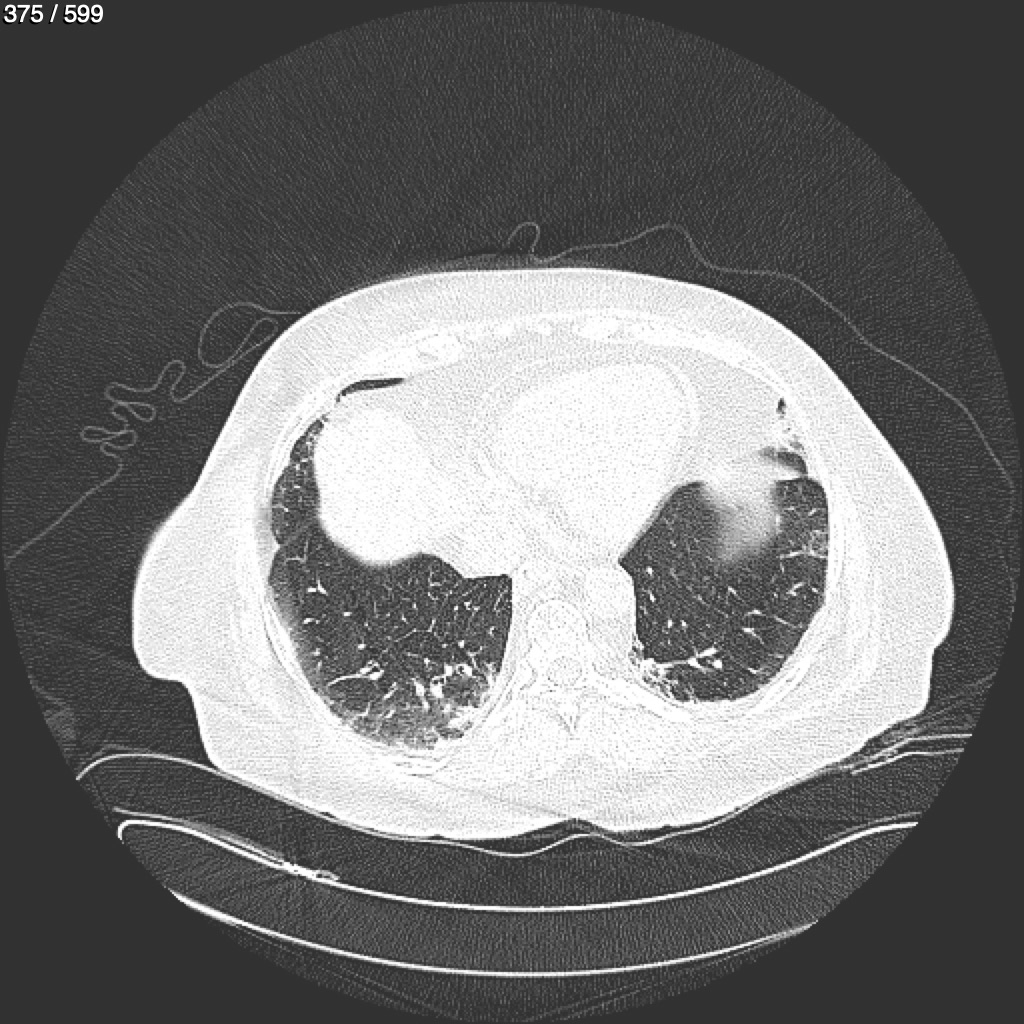

Home G​l​o​r​i​a​ ​G​l​a​d​y​s​ ​B​e​a​s​l​e​y​ ​-​ ​T​ó​r​a​x​ ​T​o​r​a​x​_​S​i​m​p​l​e​ ​(​A​d​u​l​t​o​)